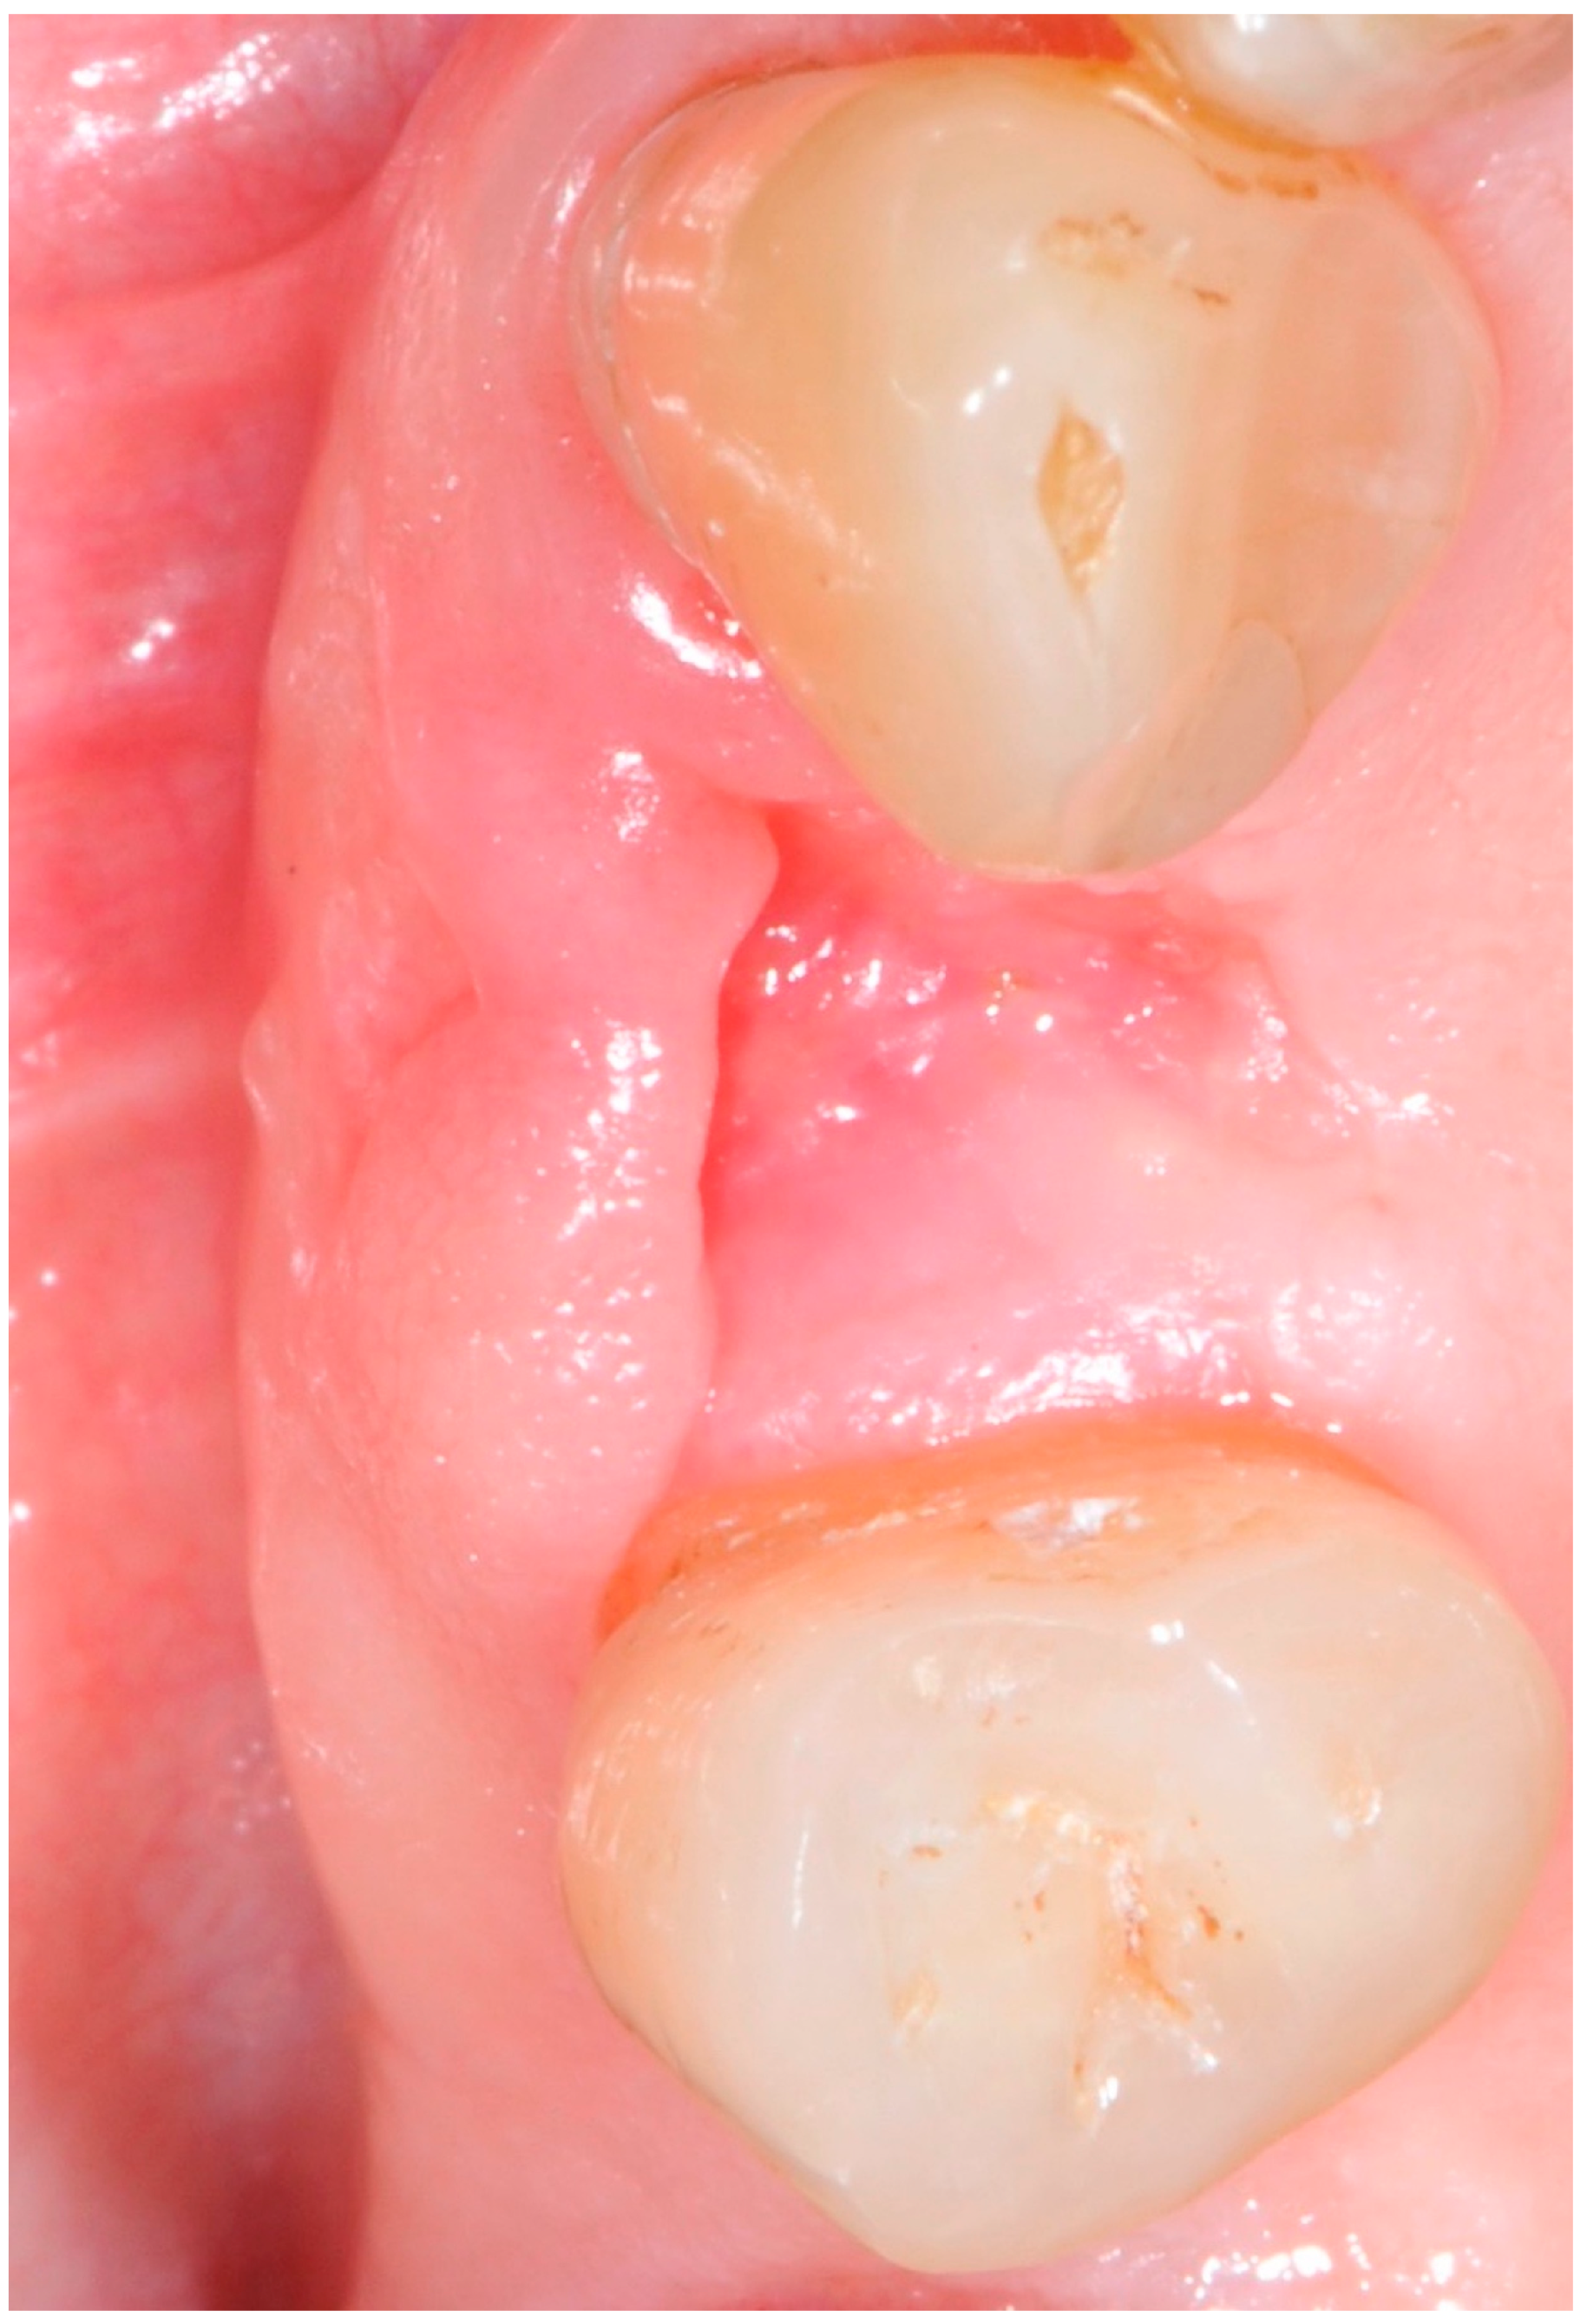

5.4. Surgical Technique

5.5. Implant Placement